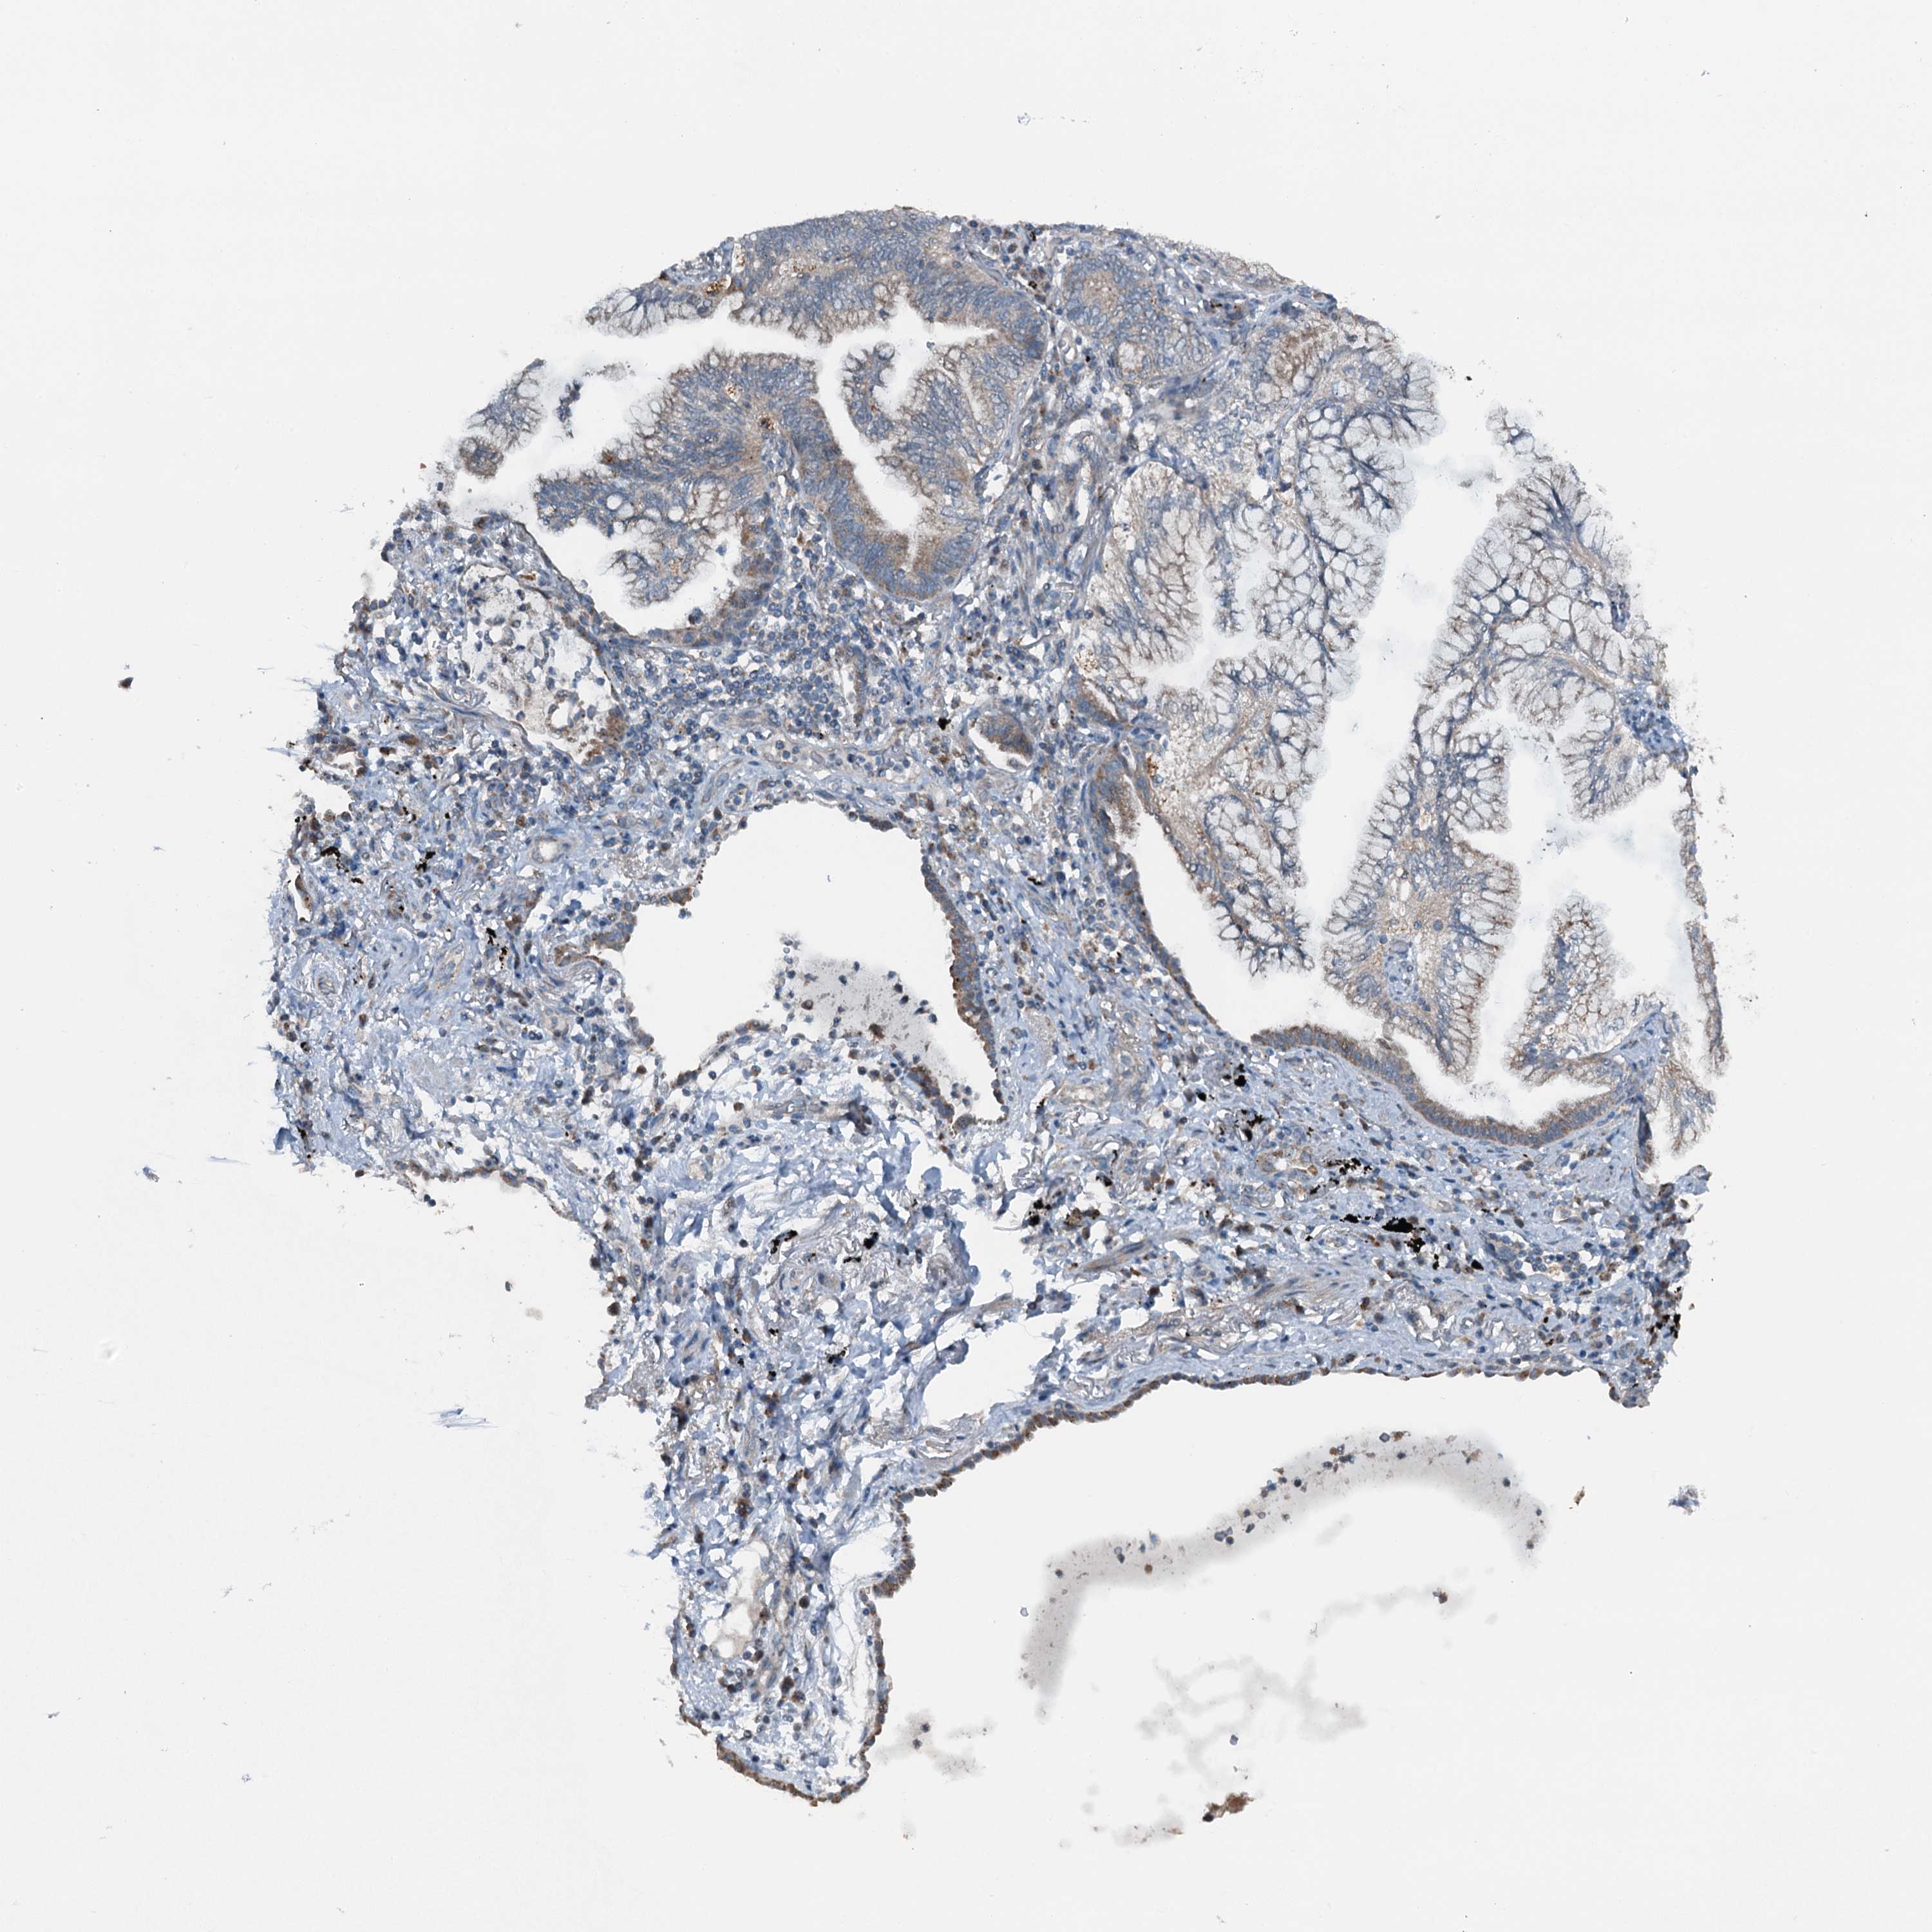

CANCER LUNG CANCER Show tissue menu

Lung cancer

Human cancer

Lung adenocarcinoma

Lung squamous cell carcinoma